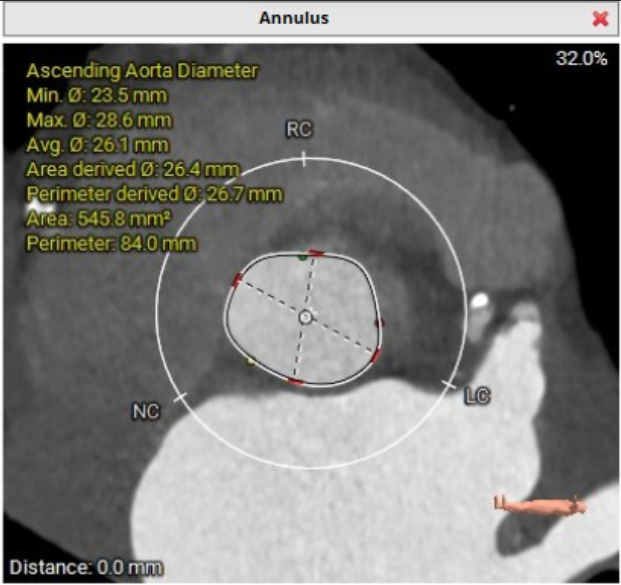

2026年伊始,TaurusTrio经导管主动脉瓣系统在复旦大学附属中山医院,浙江大学医学院附属第二医院,中国医学科学院阜外医院,首都医科大学附属北京安贞医院,四川大学华西医院等多家临床中心成功开展上市后全国首批植入。这不仅是TaurusTrio正式走向广泛临床应用的重要里程碑,更标志着中国单纯主动脉瓣反流介入治疗正式迈入了“心键合璧”的全新纪元。